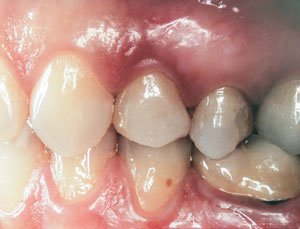

Second-stage surgery was performed after 4 months (Figure 8); healing abutments were placed and the soft tissue was allowed to heal for 5 more weeks. Then, splinted porcelain-fused-metal (PFM) crowns supported by custom gold abutments were delivered (Figure 9 and Figure 10).

Figure 9  Final implant-supported PFM restorations.

Figure 10  Posttreatment radiograph, after cementation of the final restorations.

Figure 9

Figure 10